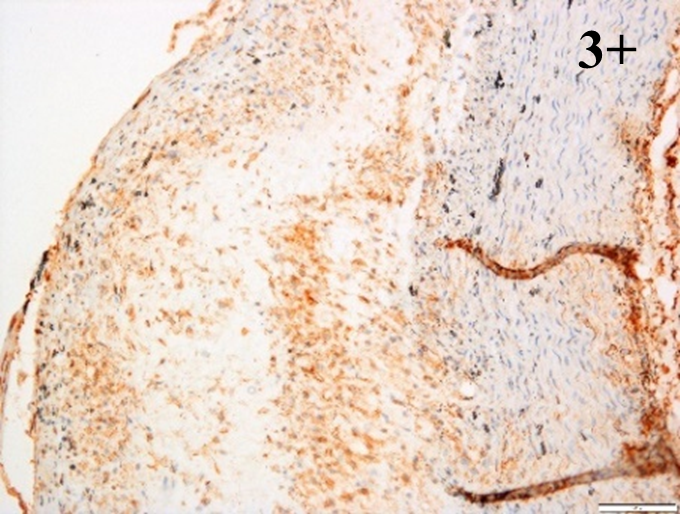

Immunoreactions of ICAM-1, VCAM-1, e-selectin, IL-6, IL-8, NF-

According to the percentage endothelial staining of cells, semi-quantitative

scores were applied. Score: 0 (negative); 1+ (1–10% positive cells); 2+

(11–25% positive cells) and 3+ (

Medium to high expressions of adhesion molecules, such as ICAM-1, VCAM-1 and

e-selectin were observed in the aortas of rabbits fed with HCD. This represents

the initiation of the lesion stage, where the endothelial cells have been

stimulated by the ox-LDL to express the adhesion molecules, which could lead to

the recruitment of monocytes and transmigrate into the intima by diapedesis as

well as differentiate into pro-atherogenic macrophages [47]. An increased

expression of pro-inflammatory biomarkers, such as IL-6, IL-8 and NF-